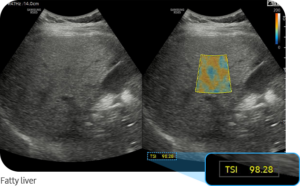

Die moderne Ultraschall-Elastographie ermöglicht eine präzise und nicht-invasive Beurteilung der Lebergesundheit. Dabei können sowohl der Grad einer Verfettung (Steatose) als auch strukturelle Veränderungen wie eine Fibrose oder beginnende Zirrhose frühzeitig erkannt werden.

Je höher die gemessene Gewebesteifigkeit, desto wahrscheinlicher ist eine fortgeschrittene Lebererkrankung. Die Messwerte werden in Kilopascal (kPa) angegeben und erlauben eine Einschätzung des Fibrosegrades.